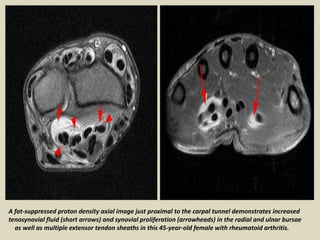

A fat-suppressed proton density axial image just proximal to the carpal tunnel demonstrates increased

tenosynovial fluid (short arrows) and synovial proliferation (arrowheads) in the radial and ulnar bursae

as well as multiple extensor tendon sheaths in this 45-year-old female with rheumatoid arthritis.